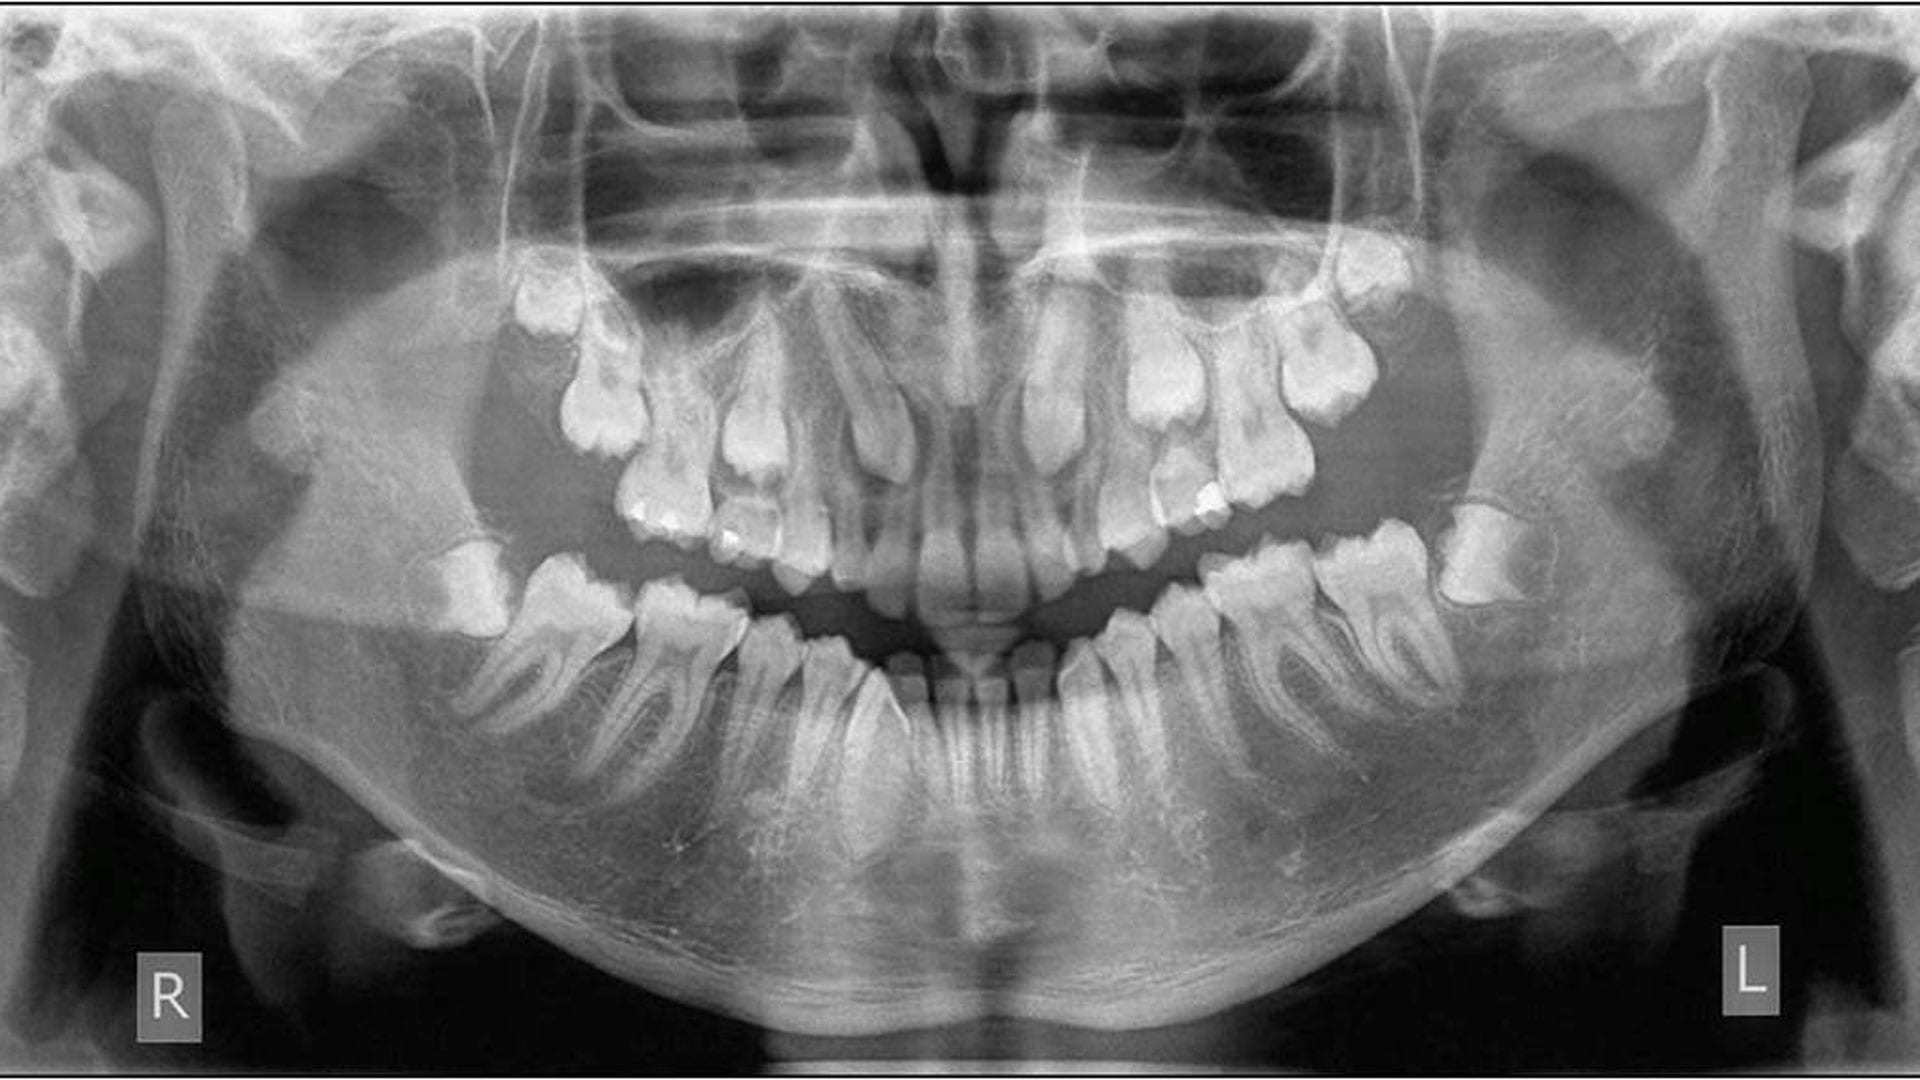

It’s important to note that the lack of pain does not indicate a clean bill of oral health with no underlying dental issues. We recommend patients to take a panoramic x-rays at least once every 5 years to identify any underlying issues as early as possible, including impacted wisdom teeth.

Fully Equipped With X-Rays

Our dental clinics are fully equipped with X-ray imaging equipment to accurately diagnose wisdom tooth impaction prior to surgery in order to provide our patients with a seamless and hassle-free experience.